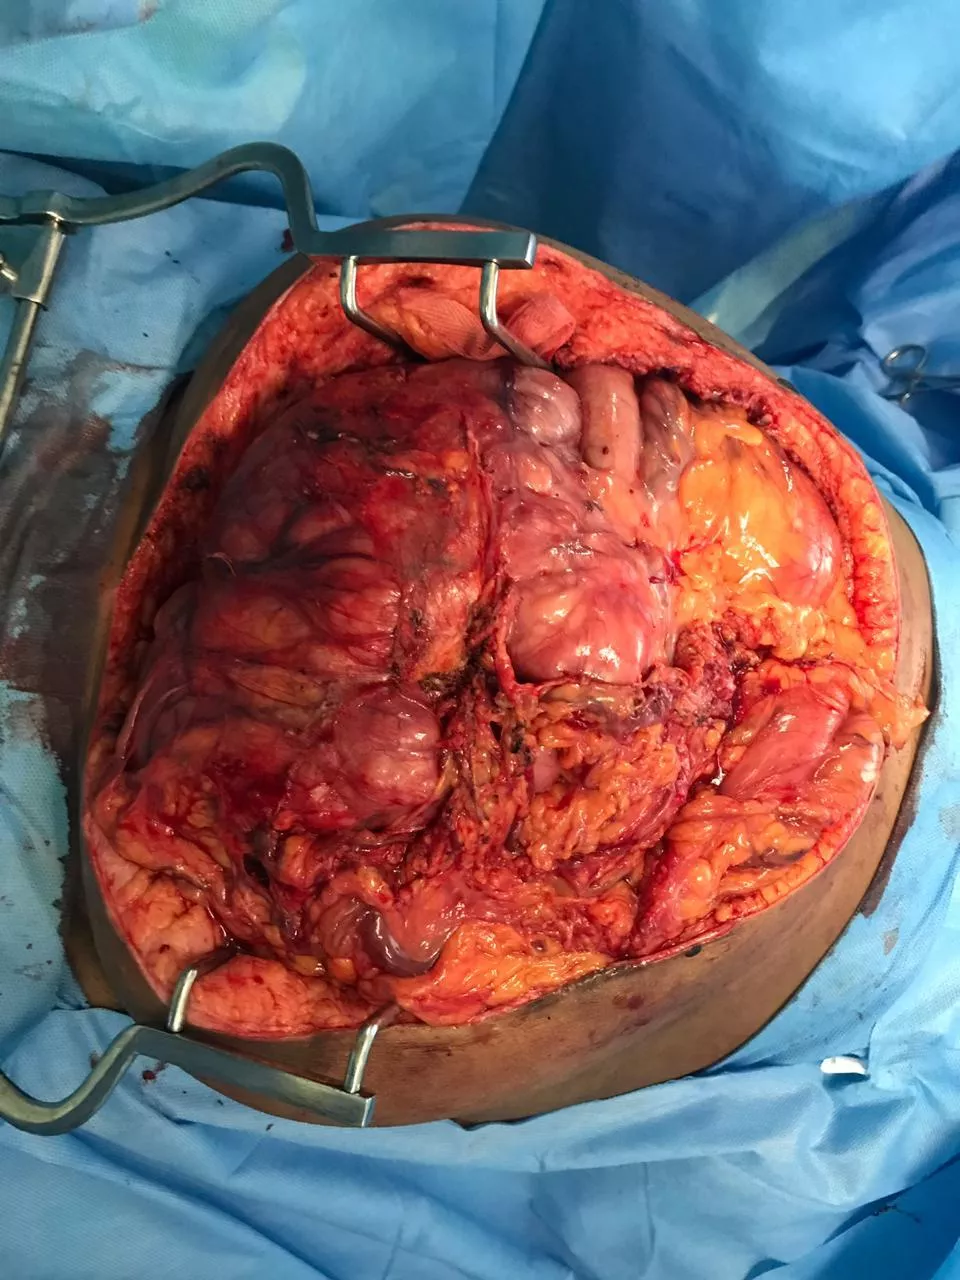

The Team successfully removed 7 kilograms weighing cancer tumour "Retroperitoneal Sarcoma” in 7 hours long surgery and set a new World Record for International Book Of Records.

A lady patient who was carrying a tumor for 2 years had undergone surgery at Gateway Hospitals on September 2nd, 2019. The organs were removed as a single specimen involving the right kidney, right ureter, right ovary, right colon (Cecum and ascending colon), ileum, retroperitoneal tumor, and lymph nodes. The patient survived after the major surgery.